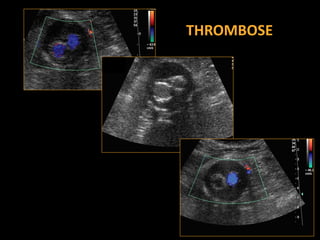

THROMBOSE

‒ Complications: plicature, thrombose, endofuite

– sténoses ou thromboses (Doppler)